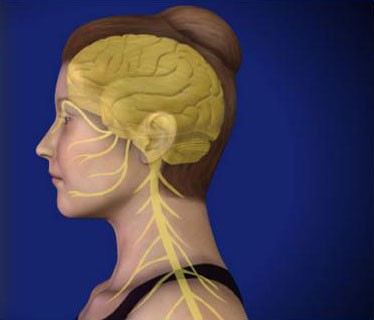

Riverside Pain Physicians is the leading provider of head, neck, and spine treatments in Jacksonville, FL, and the surrounding areas. We offer a comprehensive diagnosis for each patient so we can effectively uncover the cause of the pain. This allows us to fully treat the injury using a customized treatment plan. We recognize that there may be different factors causing an individual to experience localized pain. That is why we take the time to find out all of the potential causes prior to developing a treatment plan. Whether we are providing head pain treatment, neck pain treatment, or spine pain treatment, our patients are assured of receiving the highest levels of quality care.